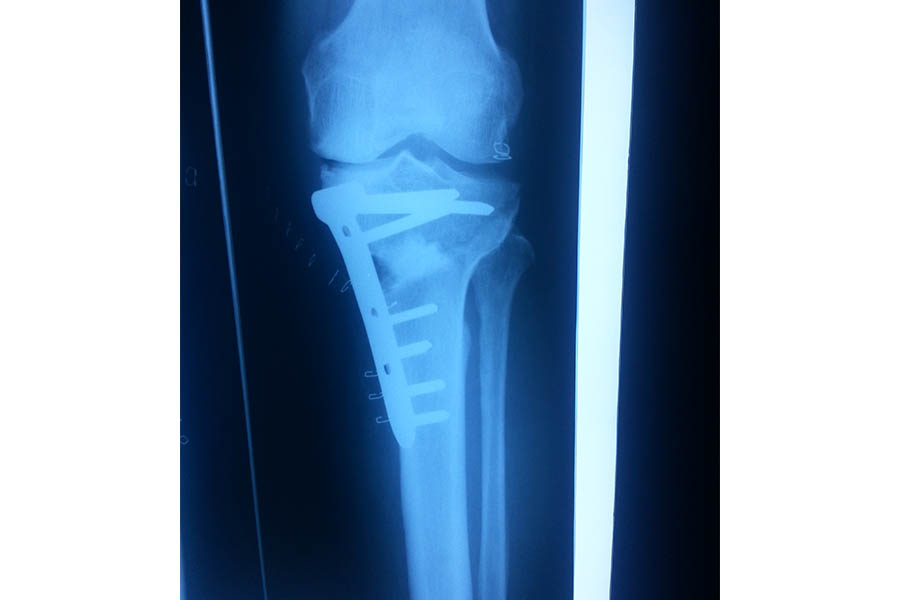

Trauma

Case 1